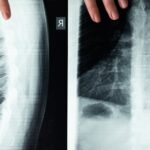

La décompression neurovertébrale est une méthode non invasive qui utilise une traction douce pour éliminer la pression sur les nerfs et les disques intervertébraux. Cette technique est de plus en plus reconnue pour son efficacité dans le traitement des douleurs chroniques, notamment celles causées par des hernies discales et d’autres conditions vertébrales. En intégrant des systèmes assistés par ordinateur, cette approche permet une personnalisation optimale du traitement.

Souffrir d’arthrose de la colonne vertébrale peut bouleverser le quotidien par la douleur articulaire, la raideur cervicale ou lombaire, et la perte progressive de mobilité. Cette usure articulaire, souvent associée à une dégénérescence discale, se traduit fréquemment par un déséquilibre…

La décompression vertébrale est l’une des innovations majeures dans le domaine des soins vertébraux. Cette méthode non invasive permet de soulager la pression exercée sur les disques intervertébraux, favorisant ainsi la guérison naturelle des tissus. Grâce à des systèmes assistés par ordinateur, le traitement est personnalisé et ciblé, optimisant les résultats cliniques. Cette technique s’avère particulièrement efficace pour soulager les douleurs associées aux hernies discales et à la sténose foraminale.

La décompression neurovertébrale s’affirme comme l’une des techniques les plus impactantes pour soulager la pression sur les disques intervertébraux sans recourir à des manœuvres invasives. En éliminant la pression néfaste sur les nerfs et en favorisant la régénération des tissus, elle contribue significativement à la réduction de la douleur. Les résultats cliniques encourageants confirment son efficacité, et de plus en plus de professionnels recommandent cette approche à leurs patients.